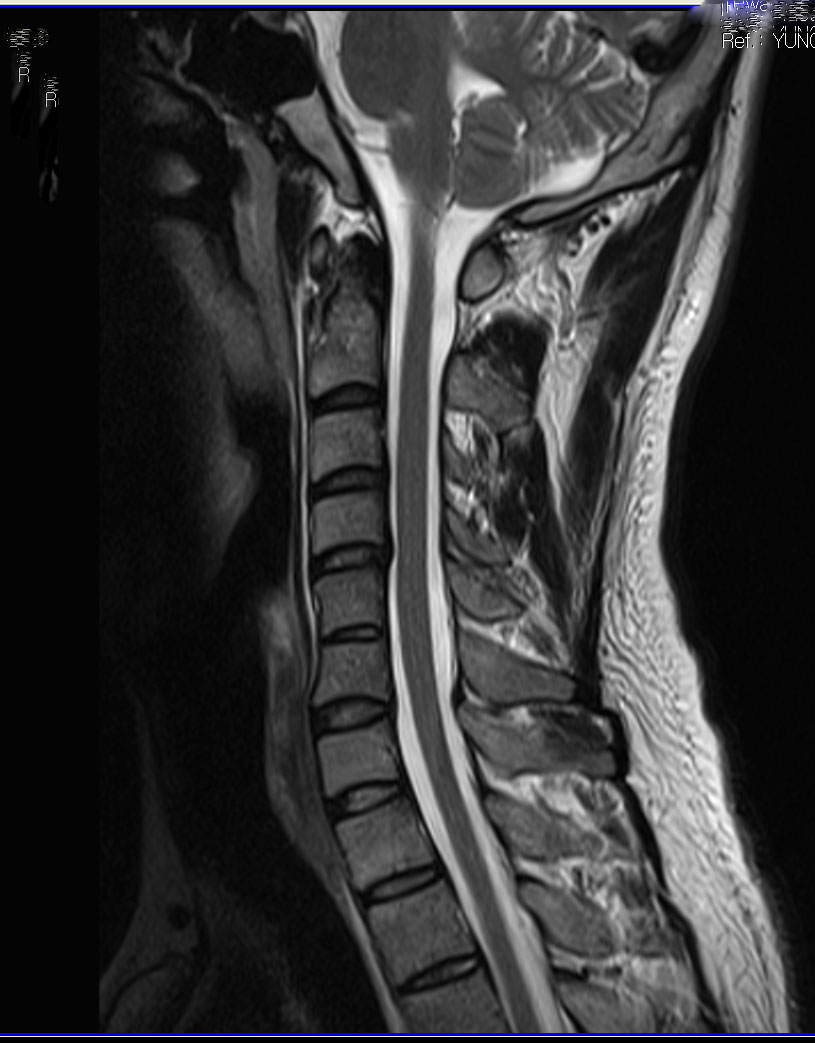

, ü Ư Ű 180 Cm ü 94 Kg 32 ȯ 1C~7C شǴ () ºҷ Ÿ ֽϴ. 1C.Ż, 1C., 1C.ڵӸ , 1C.ٽŰ, 1C.ٿ, 1C.ٺҸ, 1C.ٸǷ, 1C., 1C.ھ, 1C.߷ (), 1C.ڱӼ , 1C.ڱ ֺ ̻, 1C.ڱ ֺ , 2C.ڴ, ýŰ , 2C.ٴ, 3C.ڱ(), 4C.û°, 6C.ڸ , 6C. κ Ḳ , 6C.ھ Ḳ , 6C.ڻ , 7C.ڿʰ , () ºҷ Ÿ ֽϴ. 1T. κ , 3T.ڵ , 4T. ༺ , 4T.Ȳ, 5T.氣, 5T.ȯ ҷ, 5T.ڹ߿, 5T.к, 6T. , 6T.꿪 ĵ, 6T.ڼȭҷ 1L., ()κп ̻ ܵ. ()ũ( ߰Ż), ڸ(߹), Ͽ ũ(߰Ż)ġ, հ , ġ, , Ḳ ġ Ǵ , , Ϳ︲, ̸, Ϳ Ҹ , ȯû Ǵ ġ Ҹ ġ ڰ, 鹫ȣ, ߵ ڰ Ǵ ġ ħ Ʈ 氨 ȭҷ ġ ͳ ˻ڷ õ MRIԿ , ũ 1. ߰ 2. 3. ũ ġ 4. 5. -> ȭҷ, |